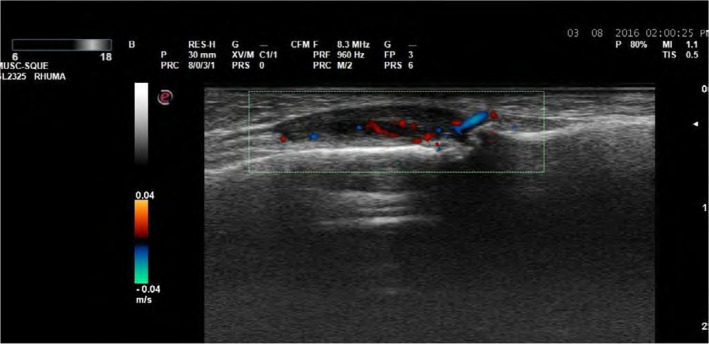

Abstract Image